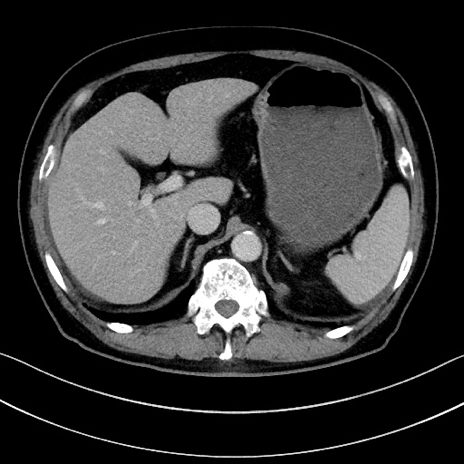

症例15(横断像)

【症例】70歳代男性

【主訴】腹痛

【現病歴】今朝から腹痛あり。全体的に痛い。特に左上の方。排ガスが今日はない。冷や汗が出る。

【既往歴】直腸癌術後

【身体所見】左側腹部〜上腹部に圧痛あり。腹膜刺激症状明らかなではない。軽度反跳痛。左下腹部に術後瘢痕あり。

【データ】WBC 7700、CRP 0.02